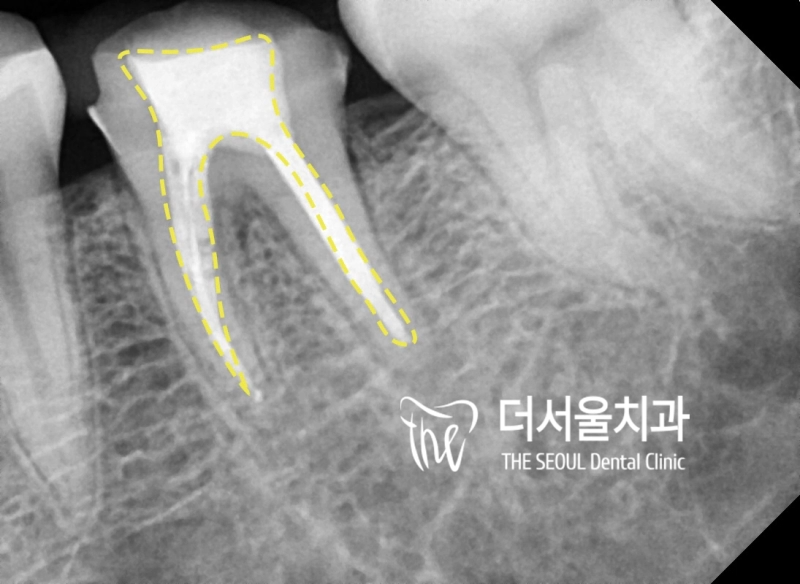

post&core (포스트&코어) 오늘은 자연치아를 살리는 마지막 방법 중 하나죠. 포스트&코어에 대한 내용을 설명드리겠습니다. 앞니 신경치료 는 어떤 과정으로